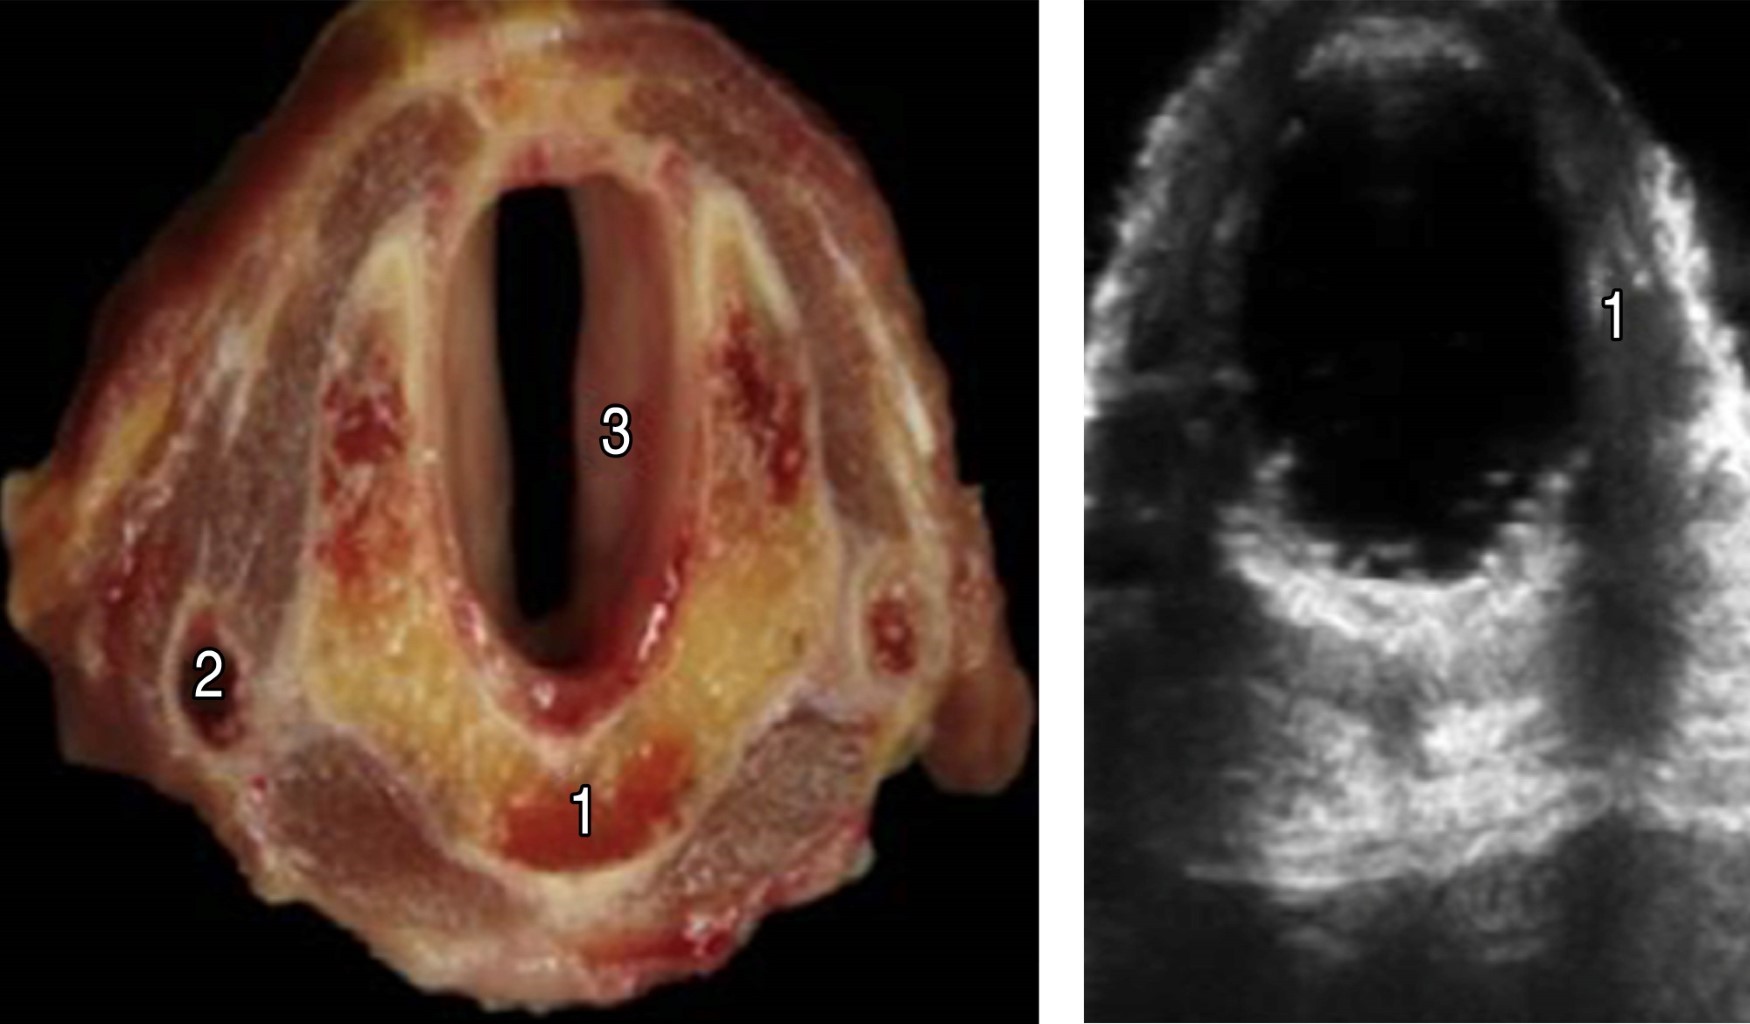

Ultrasonography is an active part of the clinical tools that we have in our arsenal for the evaluation of patients, and in the management of the airway, it can allow us to locate and mark the cricothyroid membrane prior to the management of a patient with a possible Difficult Airway. In trained hands allows the anatomy to be identified so that a cricothyroidotomy can be performed quickly and accurately in just 24.3 seconds. In this article, we show a rapid and visual systematic ultrasound localization of the cricothyroid membrane with an estimated time less than one minute. A linear high-frequency probe (5-14 MHz) should be used for exploration, as it is probably the most suitable for evaluating surface structures (within 0-5 cm below the skin surface). The positioning of the operator and the ultrasound scanner will depend on the patient's position, so in seated patients the operator is placed behind him and the ultrasound scanner in front of both, and in patients in a supine position, the operator is placed at the bedside of the patient and the ultrasound at the level of the right elbow.

Figure 3

Figure 4